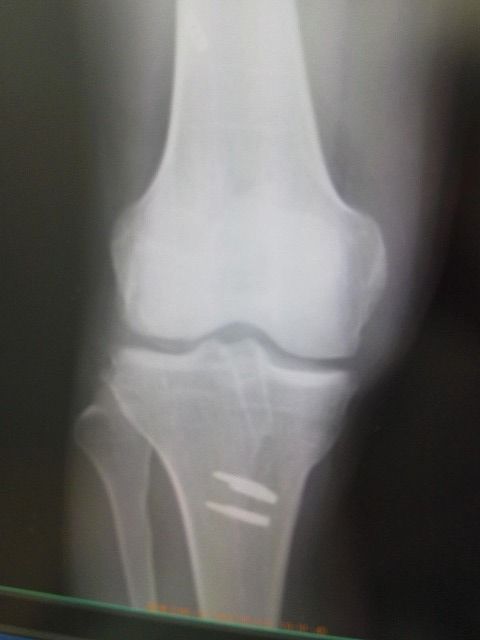

ヤマハのトップライダーの選手です。

本人の強い希望で、右膝前十字靭帯の手術後、再断裂で1か月での参戦です。

ストレッチ、EMSで強化しました。

柔軟な筋腱作りとテーピングが、結果を出しました。

内側広筋と外側広筋を使用したテーピングは威力を発揮します。

昨日の全日本選手権に参戦!  全日本ランキング2位でしたが

結果はやはり・・・でした。 しかし、3時間完走で上位ゲットしました。

ポテンシャルは高いです。

保存的治療でも十分戦えるのです!